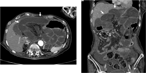

Aortic rupture due to radiation injury successfully treated with thoracic endovascular aortic repair

Yohei Kawatani and others

Journal of Surgical Case Reports, Volume 2017, Issue 5, May 2017, rjx092, https://doi.org/10.1093/jscr/rjx092